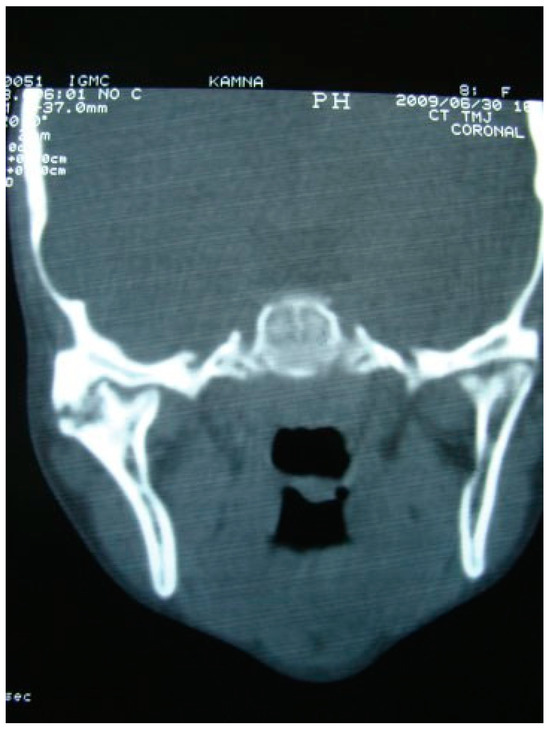

Figure 3. Preoperative coronal CT scan of right temporomandibular joint ankylosis.

The unique ability of the CCG to remodel into neocondyle could be well appreciated on the digital OPG and CT scan of the patient. The length and width of the neocondyle was very much comparable to the length of the condyle on the unaffected side at 6 years follow-up. Thus, the neocondyle formed using the costochondral cartilage was identical to the unaffected mandibular condyle both structurally and functionally. Poor socioeconomic conditions and lack of awareness coupled with poor primary health care facilities lead many of these unfortunate patients to live with this debilitating condition well into adulthood. Five such adult patients with age ranging from 17 to 36 years reported to us for treatment of TMJ ankylosis. In all these patients, ankylotic bony mass extends beyond the boundaries of the joint capsule. Alloplastic reconstruction after the release of ankylosis was our method of treatment, although high cost of condylar prosthesis led us to use 2.4 mm condylar head reconstruction plate along with temporalis muscle interpositioning in these patients. Interpositional grafts may fail to restore the ramal height in bilaterally ankylosed adult patients, so alloplastic condylar reconstruction may become the preferred choice. Advantages of alloplastic TMJ reconstruction are that the physical therapy can begin immediately, there is no need for a secondary donor site, surgery time is decreased, and alloplasts can be constructed in such a way as to mimic the normal anatomic contours of the structures they are to replace [17,18]. Wolford and Karras have suggested autologous fat transplantation as a useful adjunct to prosthetic TMJ reconstruction, as it minimizes the occurrence of excessive joint fibrosis, heterotopic calcification, and improves the range of motion [19]. However, they have categorically stated in their discussion that heterotopic bone formation is seen in multiple operated joints and joints with previously failed alloplastic implants. Another method to combat heterotopic bone formation is the use of 10 Gy of irradiation in five fractionated daily doses in the immediate postoperative period [20]. In our series, none of the patients reported with heterotopic bone formation possibly because they had undergone a single surgical procedure for managing TMJ ankylosis. The risk of fossa perforation could have been taken care by interpositioning of temporalis muscle in all these patients.

A retrospective study of post–ankylotic TMJ reconstruction of all the patients who underwent surgery for the TMJ ankylosis over a period of 11 years from 2002 to 2013, which were operated by the senior author (Y.B.), was undertaken to evaluate demographics, type of TMJ ankylosis, and modality of post–ankylotic TMJ reconstruction. The following inclusion criteria were considered for enrolling patients in this study: (1) history of traumatic injury to the face or jaws; (2) clinical and radiographic evidence of bony ankylosis at the time of presentation; (3) reconstruction of the TMJ using autogenous or alloplastic material after surgical release of ankylosis. Patients were assessed for (1) maximum interincisal opening pre and post operatively; (2) restored vertical ramal height; (3) occlusion; (4) facial symmetry; and (5) postoperative complications. Radiographic evaluation consisted of both preoperative and postoperative panoramic radiography Orthopentomogram (OPG) (Figure 1 and Figure 2) and CT scans in axial, coronal, and sagittal sections with three-dimensional reconstruction (Figure 3 and Figure 4). Surgical protocol was that the TMJ was approached through the Al-Kayat and Bramley’s incision and at least 2 to 2.5 cm resection of the ankylotic chunk was performed in all our cases. Ipsilateral and contralateral coronoidectomy was performed when required to achieve passive mouth opening. Interpositional arthroplasty was done using various materials such as temporalis fascia, temporalis muscle, and articular disc, whereas joint reconstruction was done using CCG and titanium reconstruction plate with condylar head. Intensive physiotherapy postoperatively was an integral part of protocol.